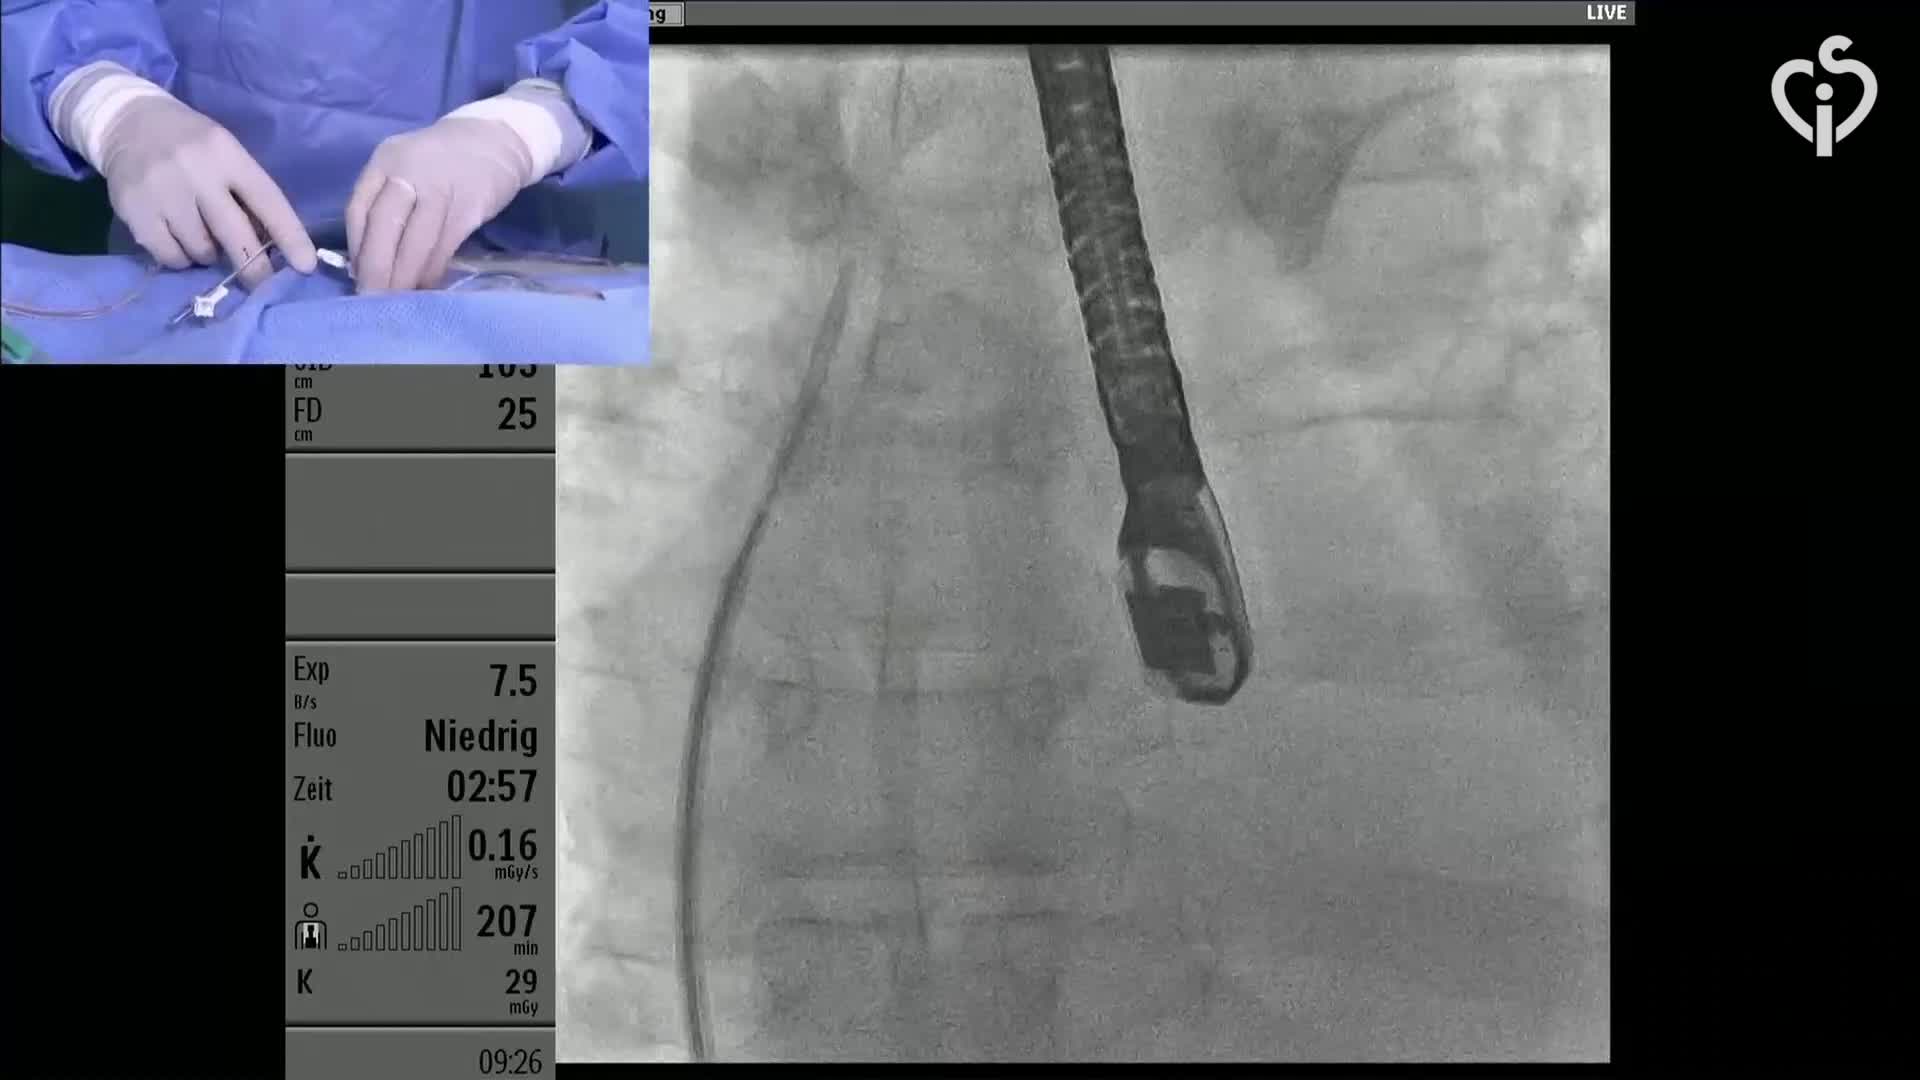

CSI CATHLAB LIVE - VSD CLOSURE WITH THE NEW OCCLUTECH PMVSD OCCLUDER (ANTEGRADE APPROACH)